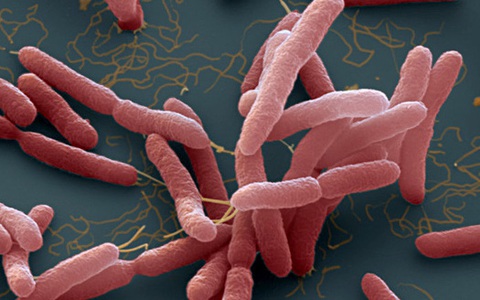

Rất nhiều ca nhiễm và tử vong do "vi khuẩn ăn thịt người" (bệnh Whitmore). Bệnh khó chẩn đoán và nhiều người còn chưa biết đến căn bệnh chết người này để phòng tránh.

CDC đã đưa ra khuyến cáo đối với các cơ sở y tế sau khi lần đầu tiên phát hiện vi khuẩn Burkholderia pseudomallei gây bệnh Whitmore trong mẫu đất và nước ở Mỹ.

TTO - Trường hợp bé gái 9 tuổi ở Đắk Lắk bị nhiễm Whitmore (do vi khuẩn Burkholderia pseudomallei gây ra, còn gọi 'vi khuẩn ăn thịt người') lại dấy lên nỗi lo lắng khi chúng xâm nhập vào cơ thể, gây tổn thương nhiều cơ quan.